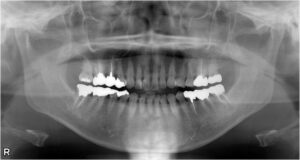

下顎小臼歯1本欠損症例

BEFORE AFTER 52歳女性/上1本欠損/インプラント埋込手術 【治療内容】 右上第二小臼歯には被せ物が入ってい…